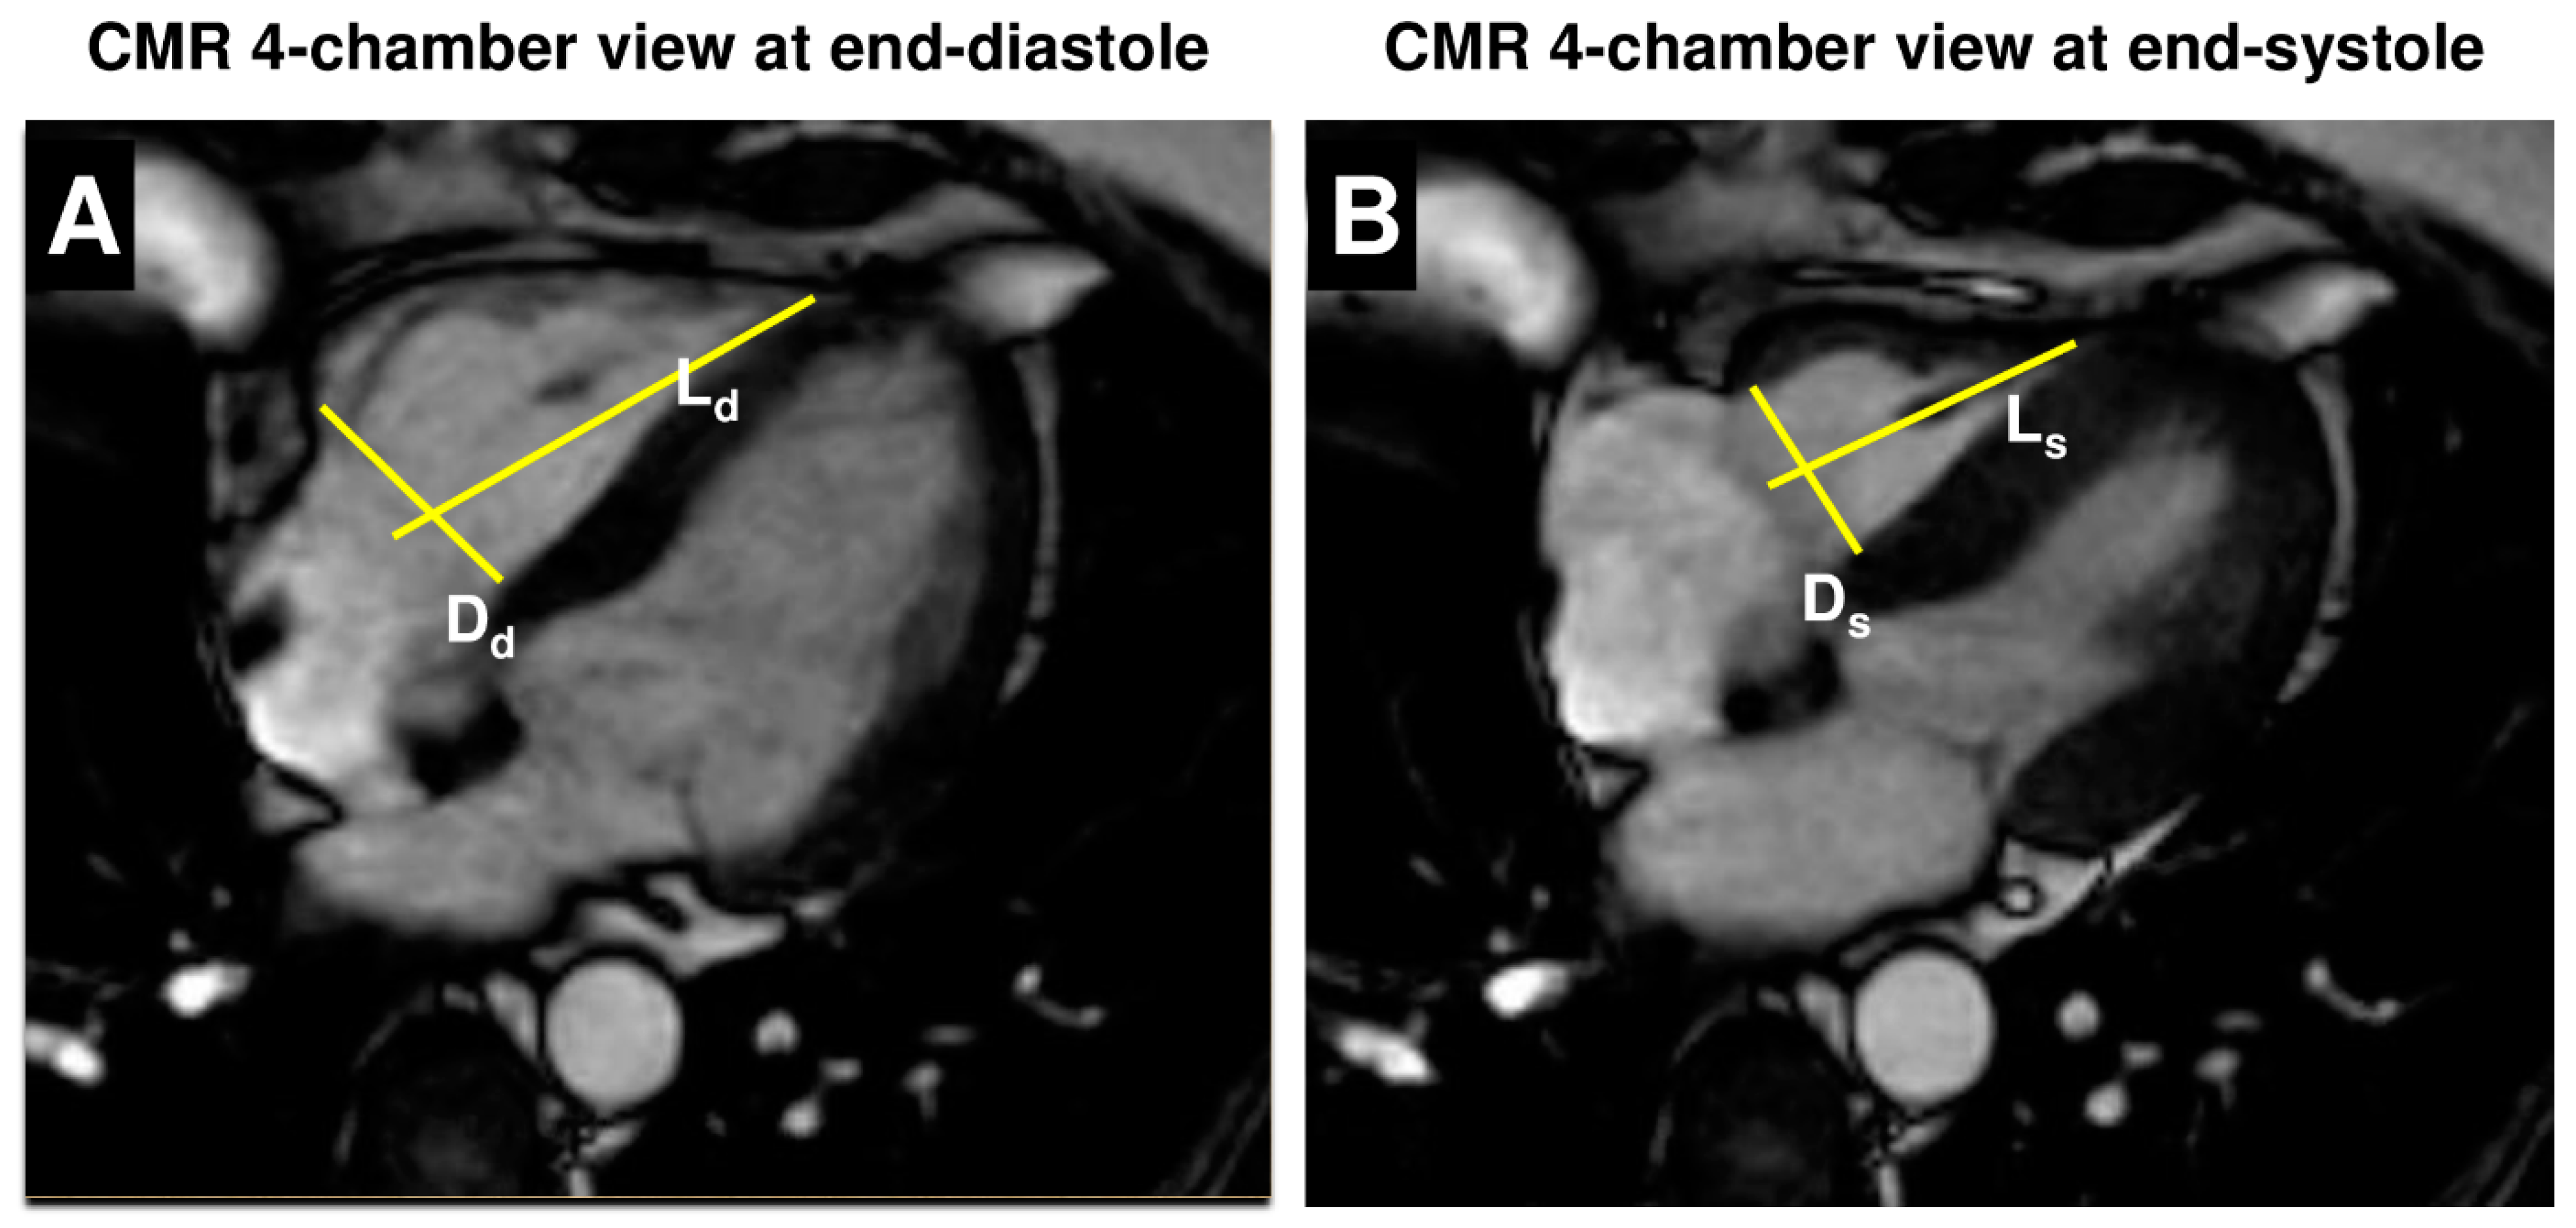

| RV Dd, cm | 4.2 ± 0.6 |

| RV Ds, cm | 3.5 ± 0.6 |

| RV Ld, cm | 7.7 ± 1.1 |

| RV Ls, cm | 6.5 ± 1.2 |